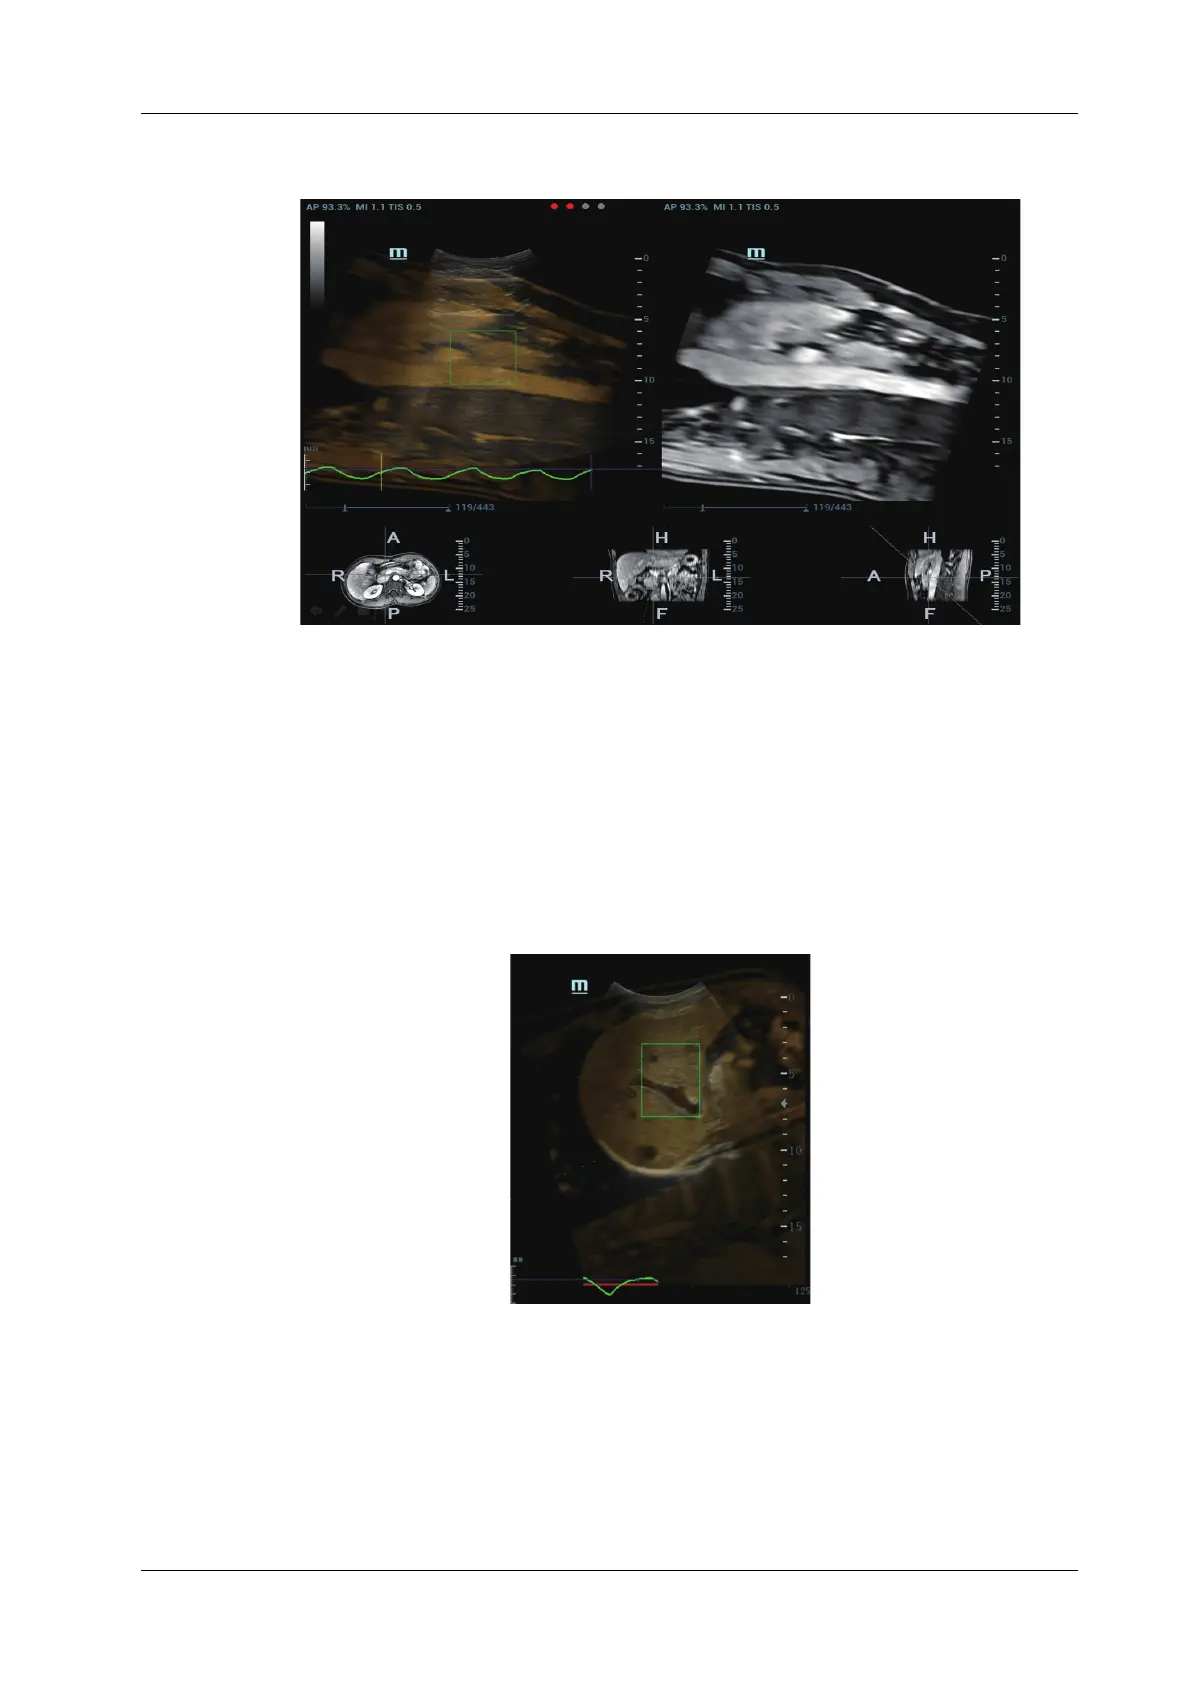

4. Tap [Motion Modeling]. If modelling succeeds, the system will play the cineloop

automatically, and ROI moves along with the motion of the respiration curve.

5. Tap [Motion Compen] to activate it. Move the probe. The Ultrasound System shows the CT

image which is processed by respiration compensation (Fusion Imaging with the respiration

compensation).

Respiration Range

The aspiration curve appears due to the active respiration depth. The respiration curve beyond the

scale becomes the straight line.

Rotate the knob beneath [Resp Range]. Respiration curve scale and the unit appear on the right-

axis.